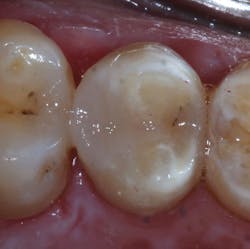

Figure 11: Preparation after completed application of Admira Fusion

Figure 12: Final radiograph of restoration

The tooth was anesthetized using 4% articaine with 1:200,000 epinephrine x 1.8 cc. The upper left posterior quadrant was isolated using a rubber dam. Following removal of the restoration (figure 4), gross caries was removed using a #6 round stainless steel slow-speed carbide followed by #6 and #4 round slow-speed polymer SmartBurs II (SS White). Complete caries removal was determined by explorer examination and evaluating the existence of cariogenic bacteria using fluorescence (Spectra, Air Techniques). A Triodent sectional matrix system (Ultradent) was placed (figure 5), followed by the application of a base layer using Ionolux RMGI (figure 6). In addition, the Ionolux RMGI was selected for this case due to its high compressive strength, approaching levels seen with the newest generation of flowable composite resins. (8,9) The Ionolux was compressed into the preparation in what was the initial layer of the open sandwich technique. Following the light-curing of the Ionolux (figures 7 and 8), Futurabond U (Voco), a dual-cure universal adhesive in a single-dose delivery system, was applied to the preparation and light-cured (figure 9). Admira Fusion (Voco), a universal light-cured, nanohybrid, organically modified ceramic (ORMOCER), was placed in 2-mm increments. Each increment was light-cured until the restoration was completed (figures 10 and 11). A radiograph was taken to evaluate the immediate success of the restoration (figure 12). The Ionolux RMGI demonstrated excellent opacity, comparable to composite resins.